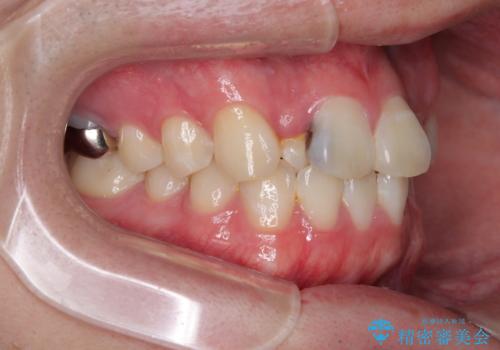

初診時の状態

・上下ともに歯がきれいに並びきらず、がたつきが見られました。

・上下の前歯の中心(正中)がずれています。

・特に上顎の幅が狭いため、下顎の歯列も内側に入り込み、歯が並ぶスペースが不足していました。